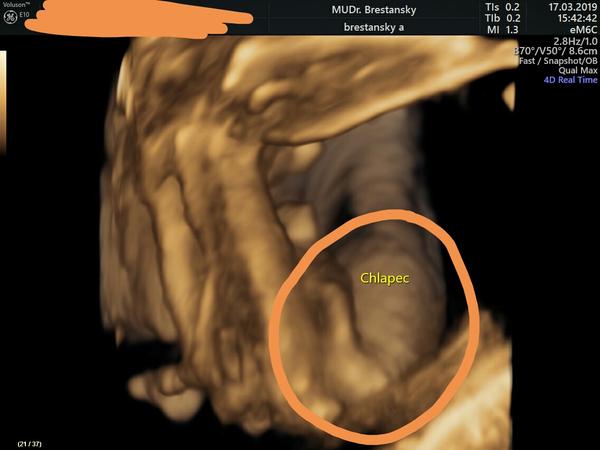

Pohlavie zo sona, myslíte, že je to chlapec, či dievča?

Ahojte, prosím vás o názor 🤗 Gynekologicka mi tvrdí,ze vraj to vyzerá na dievčatko,no mne osobne to pride ako chlapec.Co myslíte?

Prosim ta, podla čoho to je podla teba chlapec? Kde na tom obrazku vidis výbavu chlapceka?

Kolky je to týždeň? Mam 3dievcata, ale ani jednej tam po 20tt nič netrcalo.... Tiež by som sa priklonila ku chlapcovi...

Mne toto pride ako cisty chlapec. Pri dcere jej nic netrcalo,ked mala nohy od seba,tak sa jej tie pysky rozdelovali do stran k noham. Toto mi pride ako uplne mimo tela. Aj keby som si toho pindura odmyslela,ani suska tak nevytrca do priestoru. Kazdopadne daj vediet po porode,kto mal pravdu😄

@teo114 dievčatko?!